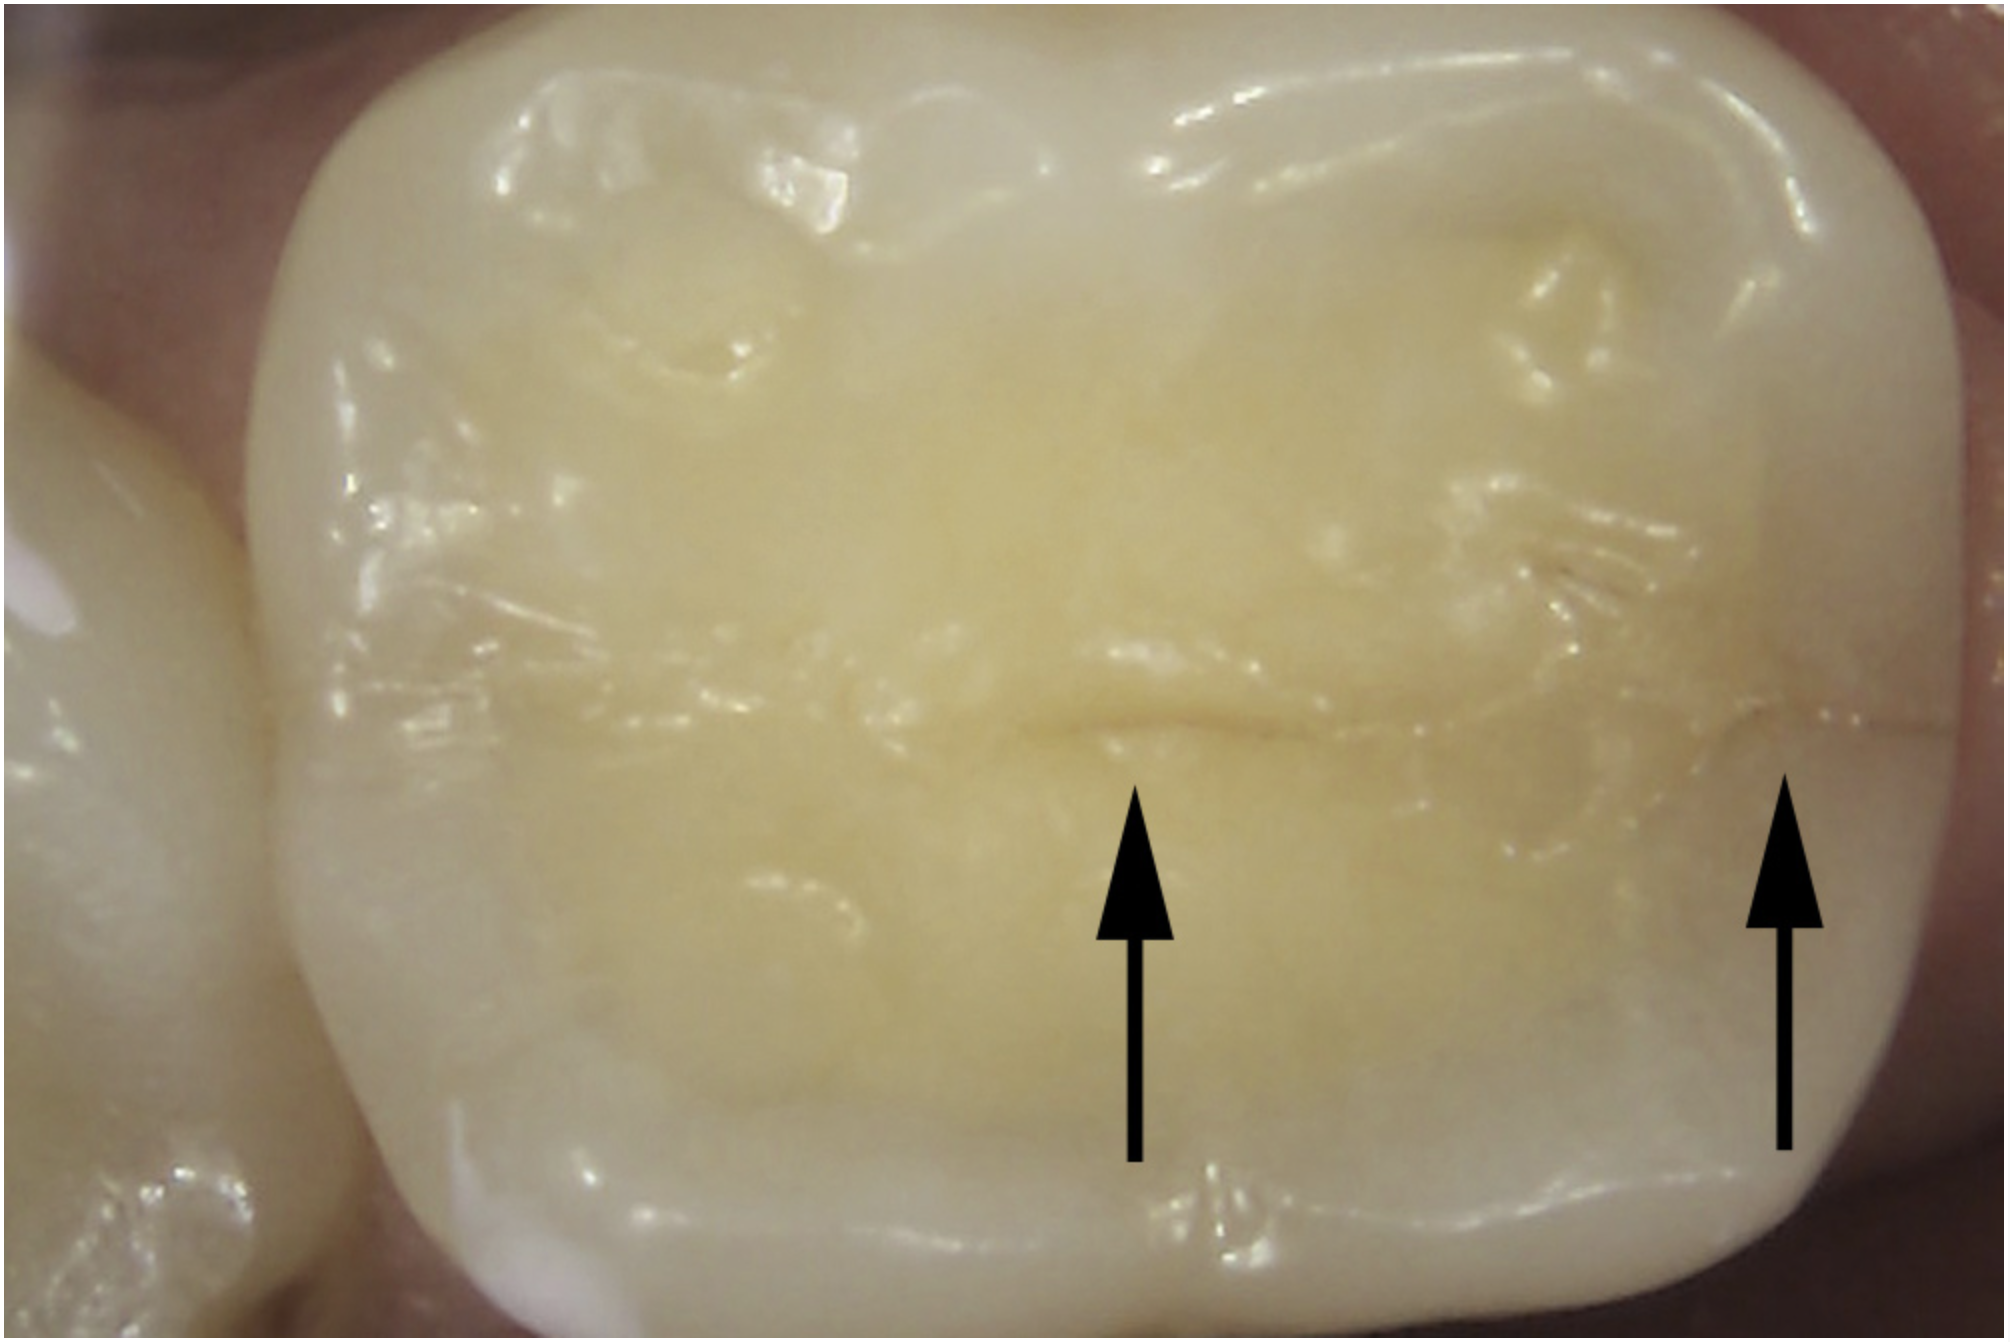

Asymptomatic vertical enamel cracks that are both naturally stained and detectable by an explorer are more likely to be treated than asymptomatic cracks that are only detectable by transillumination and dyes.19 Intervention has also been recommended for moderate- to high-risk enamel cracks, such as cracks with wedge-shaped enamel ditching, cracks that either detour from or do not follow anatomic grooves, pairs of cracks that outline an area of discolored enamel, cracks that house debris, and cracks with a brown, gray, or white corresponding halo.14

Once a significant asymptomatic enamel crack is diagnosed, to determine its extent the crack is exposed and traced using a minimally invasive exploratory fissurotomy as well as caries removal and/or existing restoration removal whenever indicated (Figure 6 and Figure 7).2,3,17 If the crack is limited to enamel and does not extend into dentin, it can be completely eliminated and treated similarly to caries whereby the condition of the remaining tooth structure dictates the type of the restoration placed and the materials used (Figure 8). For example, moderate-sized cavity preparations can support bonded direct intracoronal resin-based composite restorations (Figure 9).25 This is generally interpreted as cavity preparations in which the isthmus width is less than 50% of the intercuspal distance and the remaining enamel is sound and well supported by dentin. Occlusal adjustment, including removal of excursive interferences, might also be necessary to eliminate localized heavy occlusal forces that are predisposing the tooth to cracking.10,19,26 Occlusal guards also can be fabricated to protect teeth from the damage caused by ongoing bruxism.19

Fig 10. Stained asymptomatic enamel marginal ridge crack (arrows) of a maxillary right first molar extending to the existing restoration (mesio-occlusal view).

Figure 10

Fig 11. Exploratory fissurotomy and methylene blue dye staining revealing an underlying deep dentin crack in tooth shown in Fig 10.

Figure 11